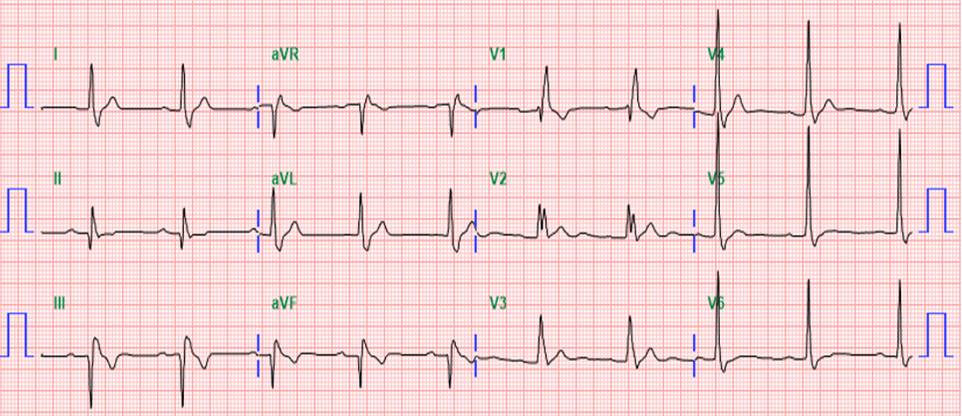

The patient is a 62-year-old man with smoking history. He sufferred from typical chest pain for six months. The baseline EKG showed sinus rhythm with RBBB. A preserved ejection fraction but basal-inferior hypokinesis was found on echocardiography. A treadmill exercise test was positive for ischemia. He therefore underwent coronary angiography.